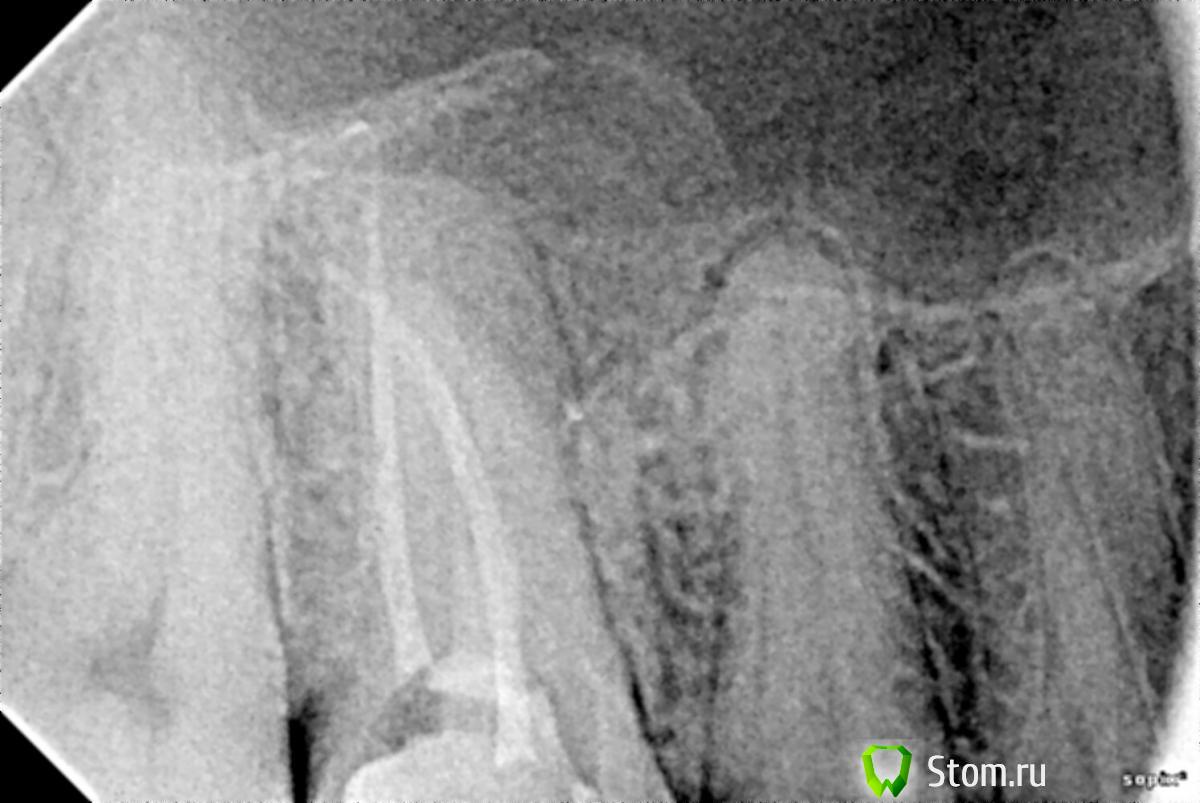

Небольшая предыстория. Несколько лет назад (точно сейчас не вспомню) в шестом верхнем правом зубе был удален нерв, а сам зуб запломбирован. Пару недель назад, при посещении стоматолога, по панорамному снимку было установлено, что каналы в этом самом зубе очень плохо запломбированы. Было принято решение зуб перелечивать. В ходе очередного приема два из трех каналов были заново запломбированы, а вот с третьим возникли трудности. Подробности точно не сформулирую, но что-то вроде "маленькое устье канала... материал вижу, но попасть сложно... необходимы специальные очки... немного кровит". В итоге доктор решил пока не трогать третий канал, поставил временную пломбу, сказал прийти через два дня на третий. А, еще предупредил о возможных болевых ощущениях при накусывании.

В течении этого дня, ночи и первой половины дня следующего, так все и было. Болезненные ощущения при накусывании, ненадолго задерживающиеся после. А вот на вторую ночь зуб начал болеть очень сильно, болел всю ночь, весь следующий день и вторую ночь. Также на вторую ночь поднялась температура до 37,5. Отека, припухлости и т.п. не наблюдалось. Когда прибежал к доктору, он сделал два снимка (их и прилагаю), удалил временную пломбу и сказал, что долечивать канал и зуб в целом следует после того как пройдет боль.

По описанной симптоматике и снимкам, по возможности, прошу консультации. А именно:

- возможные причины столь сильной боли?;

- насколько верен/профессионален/адекватен ситуации предложенный план лечения?;

- качественно ли выполнена работа по пломбировке двух каналов?

P.S. Усматривается ли на пятом зубе (по снимку справа от пломбируемого) воспалительный процесс в районе апикального отверстия?